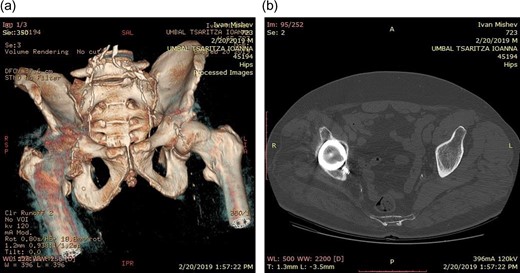

Life-size 3D model was printed from a converted file containing the computed tomography (CT) scan of one patient with severe acetabular defects waiting for total hip revision surgery. The 66-year-old male had a background of coxarthrosis. He underwent total hip arthroplasty of his right hip in February 2017. The preoperative CT scan and X-Ray of the pelvis showed large right-sided pelvic defect and severe acetabular defect (Figs 1 and 2). The patient had history of cardio-vascular comorbidity and underwent 2 week specific antihypertensive therapy preoperatively.

Preoperative radiograph demonstrating large acetabular defect with screw penetration.